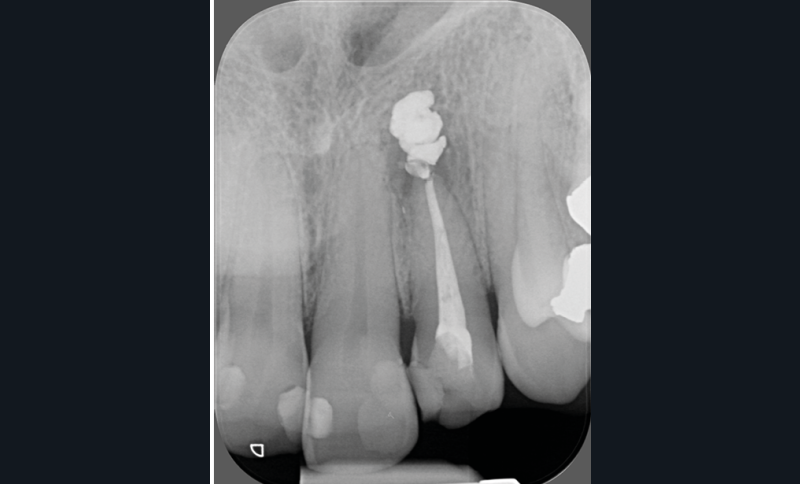

- une pathologie péri-radiculaire ne guérit pas à la suite d’un (re)traitement (fig. 1a-b) ;